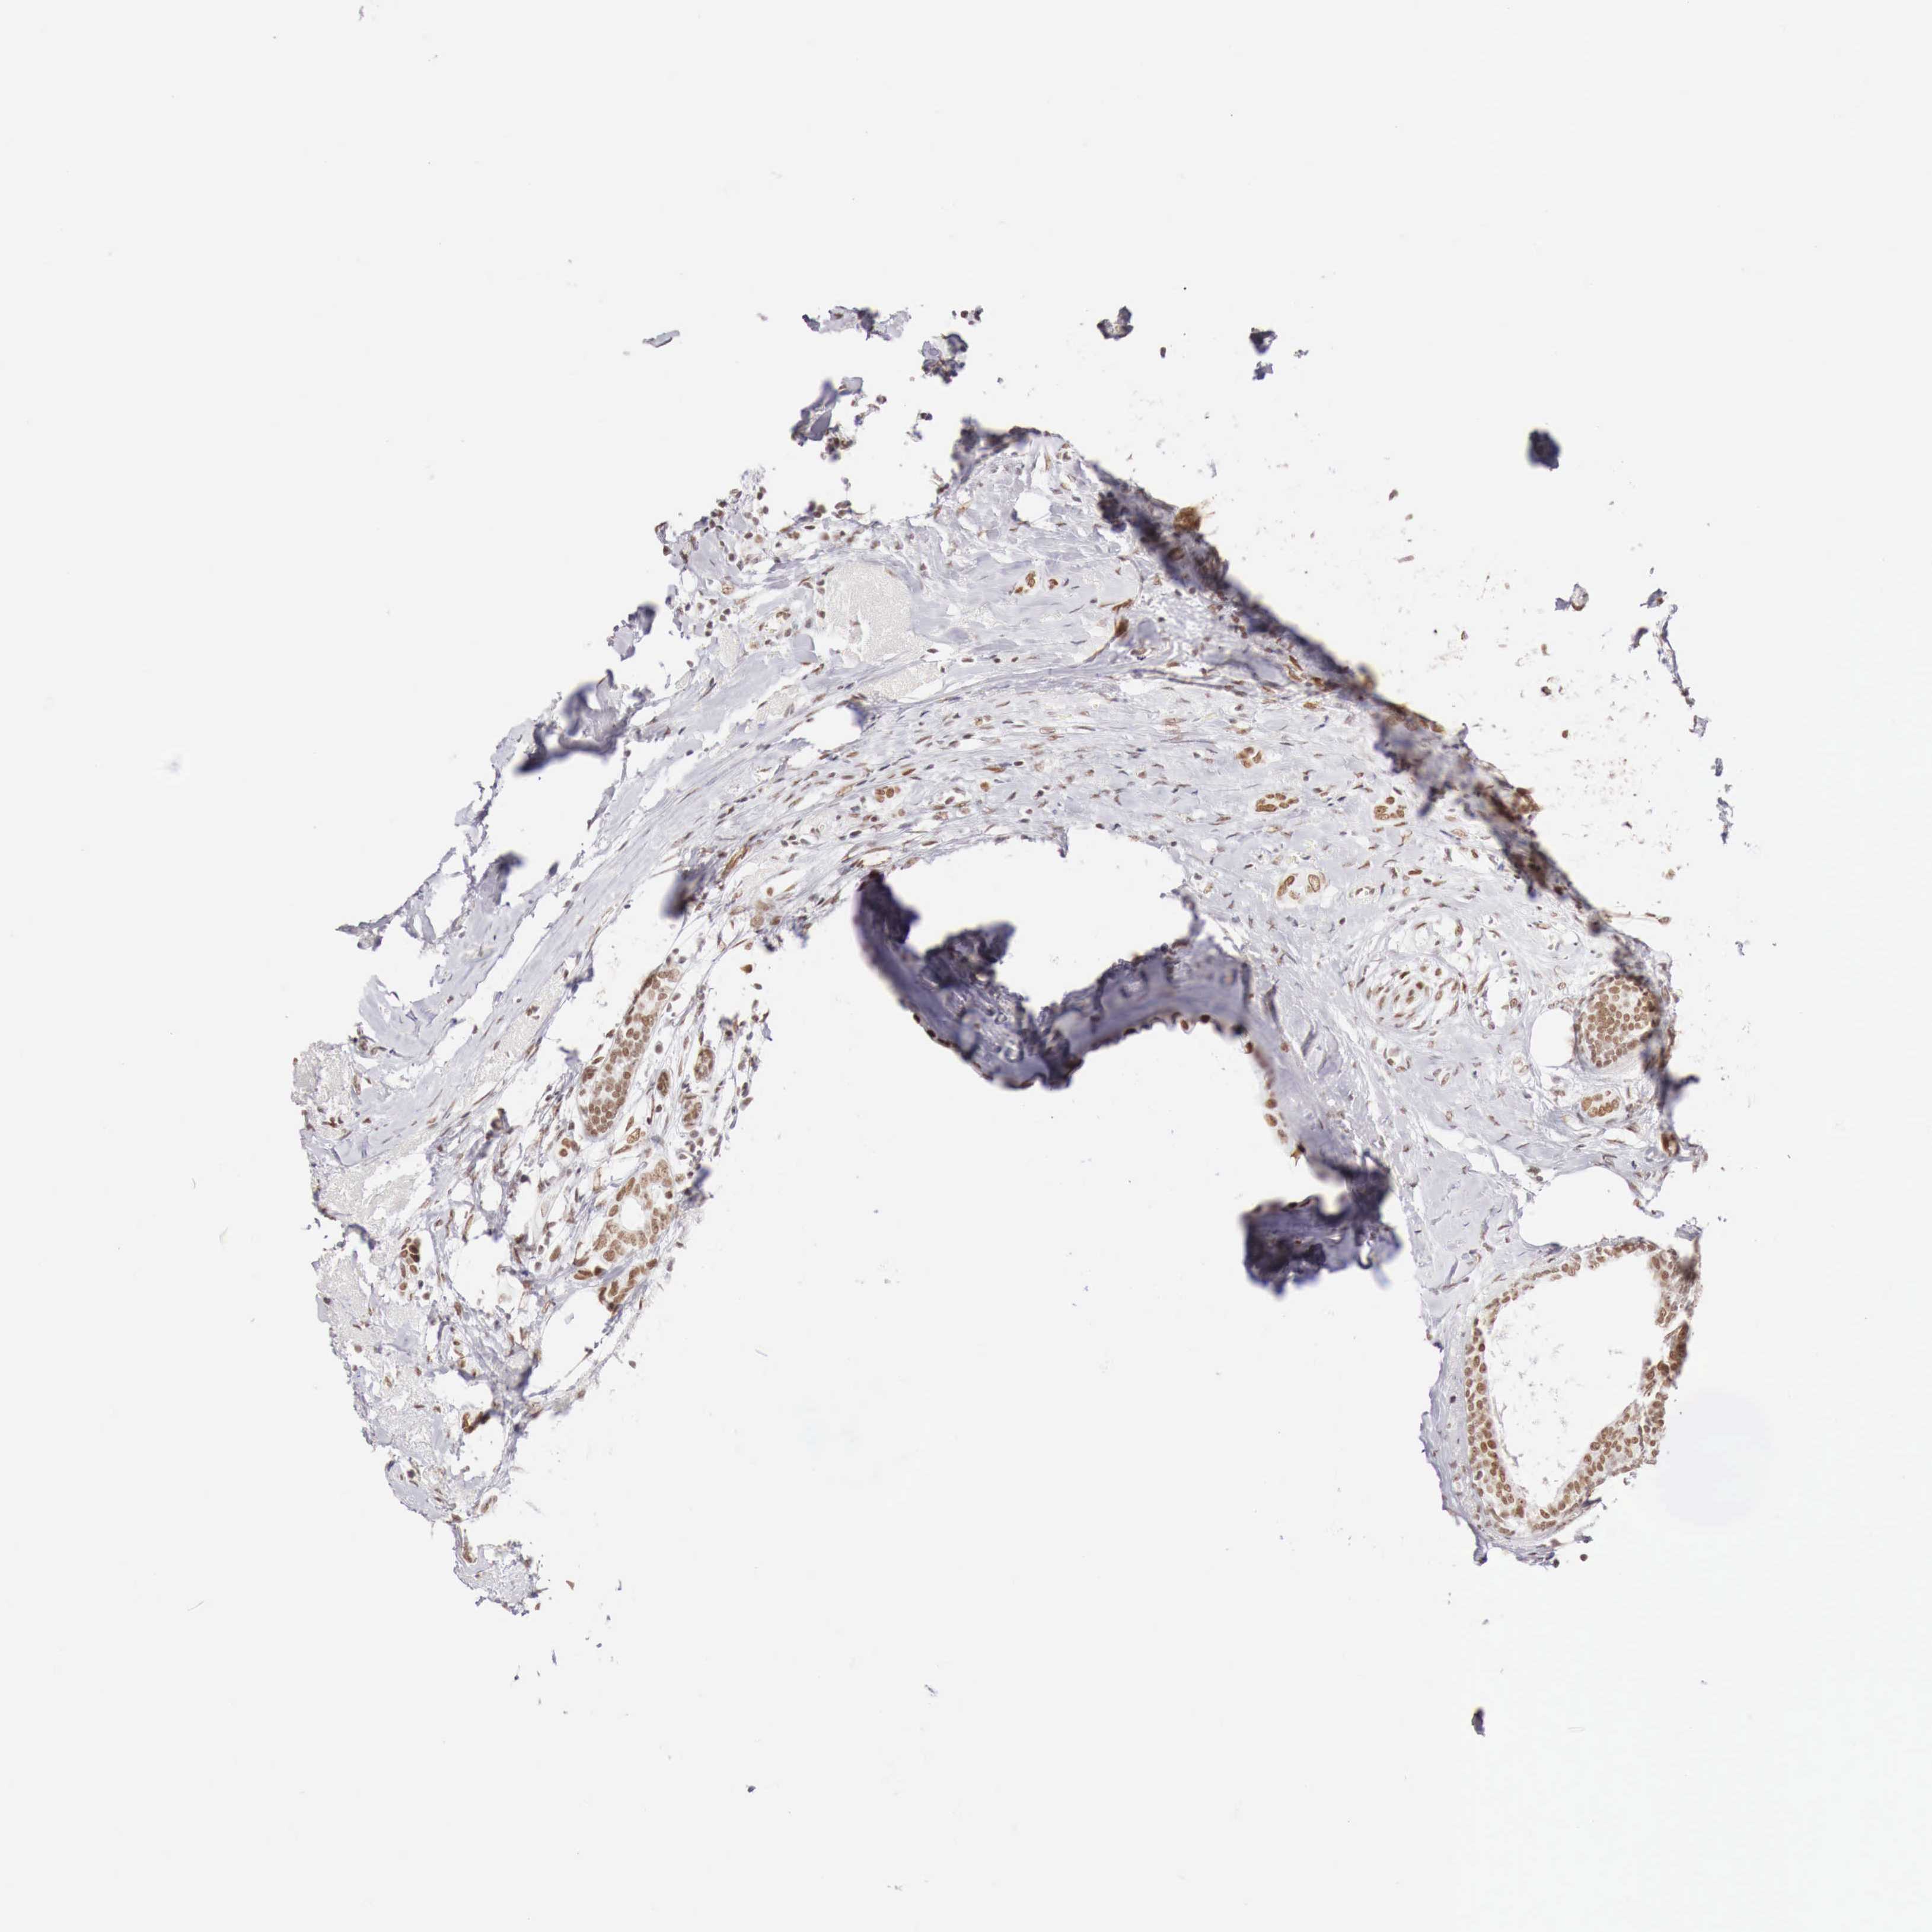

BRCA TCGA BRCA VALIDATION PROTEIN EXPRESSION

ANTIBODIES

AND

VALIDATION